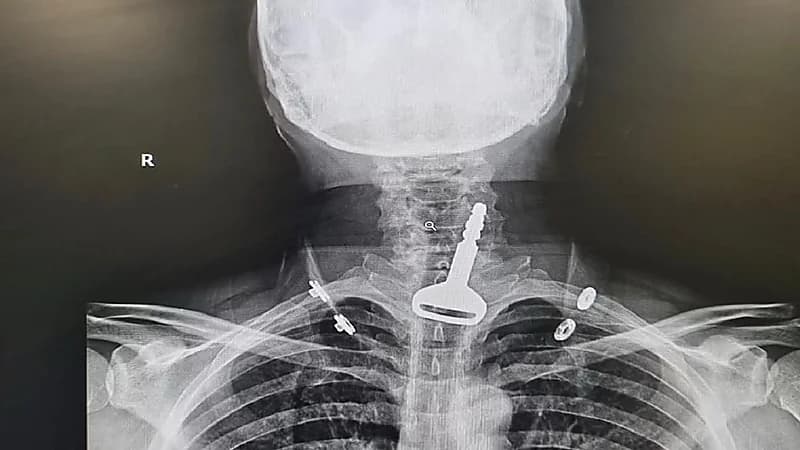

كاد شخص أربعيني في القنفذة أن يفقد حياته، بعد ابتلاعه مفتاح سيارة، فيما تمكن فريق طبي من إنقاذ حياته.

ونجح الفريق الطبي في استخراج مفتاح سيارة من الجهاز التنفسي للمريض، وذلك من خلال عملية استغرقت 15 دقيقة عن طريق المنظار.

وبحسب الفريق الطبي،فإن المريض كان يلهو بالمفتاح ما أدى لابتلاعه، حسب ما توضح خلال الكشف.